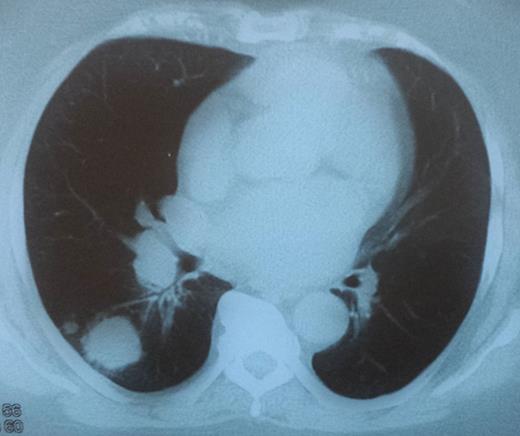

A CT scan showing a 6.2-cm mass pressuring and infiltrating the trachea and surrounding soft tissue.